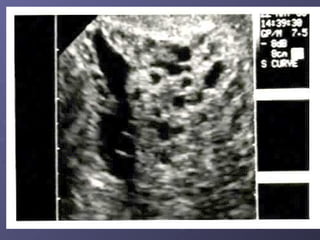

Diagnosis: U/S usually very sensitive – generalized swelling (snow-storm )

U/S usually very sensitive – generalized swelling (snow-storm )